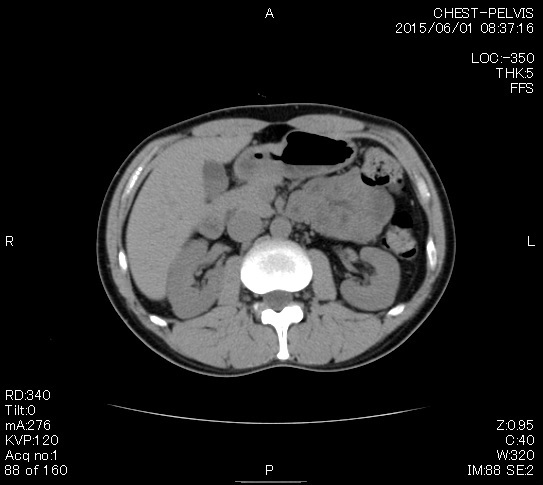

検査結果

マーカー、CT画像、問題なし!!

今回も血液検査結果は正常値のパレード!

唯一BUNがちょっとだけ基準値を超えた。

やっぱりヨメによる毎日の健康的な食事の積み重ねの結果だね。